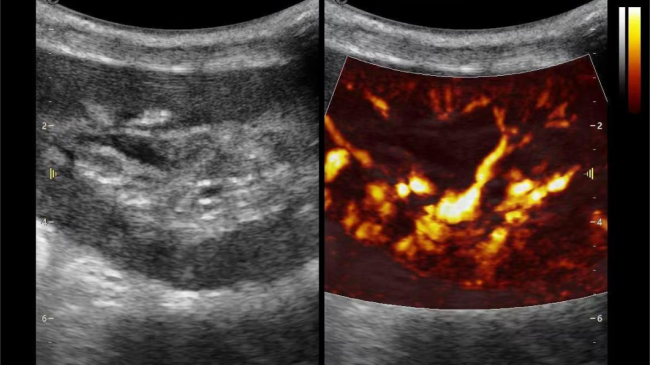

3) 通过血管指数(VI)定量评估局部血管密度,以定量化数据实时监测血流灌注情况,预判肾功能恢复情况;

肾脏的灌注评估,RI/VI量化数据

超微视血流显像评估肾移植术后灌注情况

这一项无创、无辐射操作简便且无需造影剂的黑科技,相当于用"高速摄像机"记录血液细胞的运动轨迹,让血管并发症"无处遁形。

从术前评估到术中到术后,再到终身监护,当20-50μm级的超微血流信号在屏幕上跳动,我们看到的不仅是技术的精进,更是生命的律动。iPlane Vascular正在重新定义肾移植监护的标准——让医生拥有了"显微视力",让每一个微小血管的异常都无所遁形,让每一次免疫排斥的萌芽都被及时扼制。